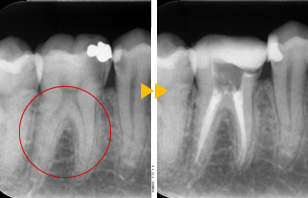

抜髄

抜髄(神経をとる処置)イニシャルトリートメント

リスクや副作用について

• 術後の痛み、違和感、穿孔、歯根破折、器具の破折がおこる場合があります。

• 根管治療後に、再治療、外科処置、抜歯などの処置が必要となる場合もあります。